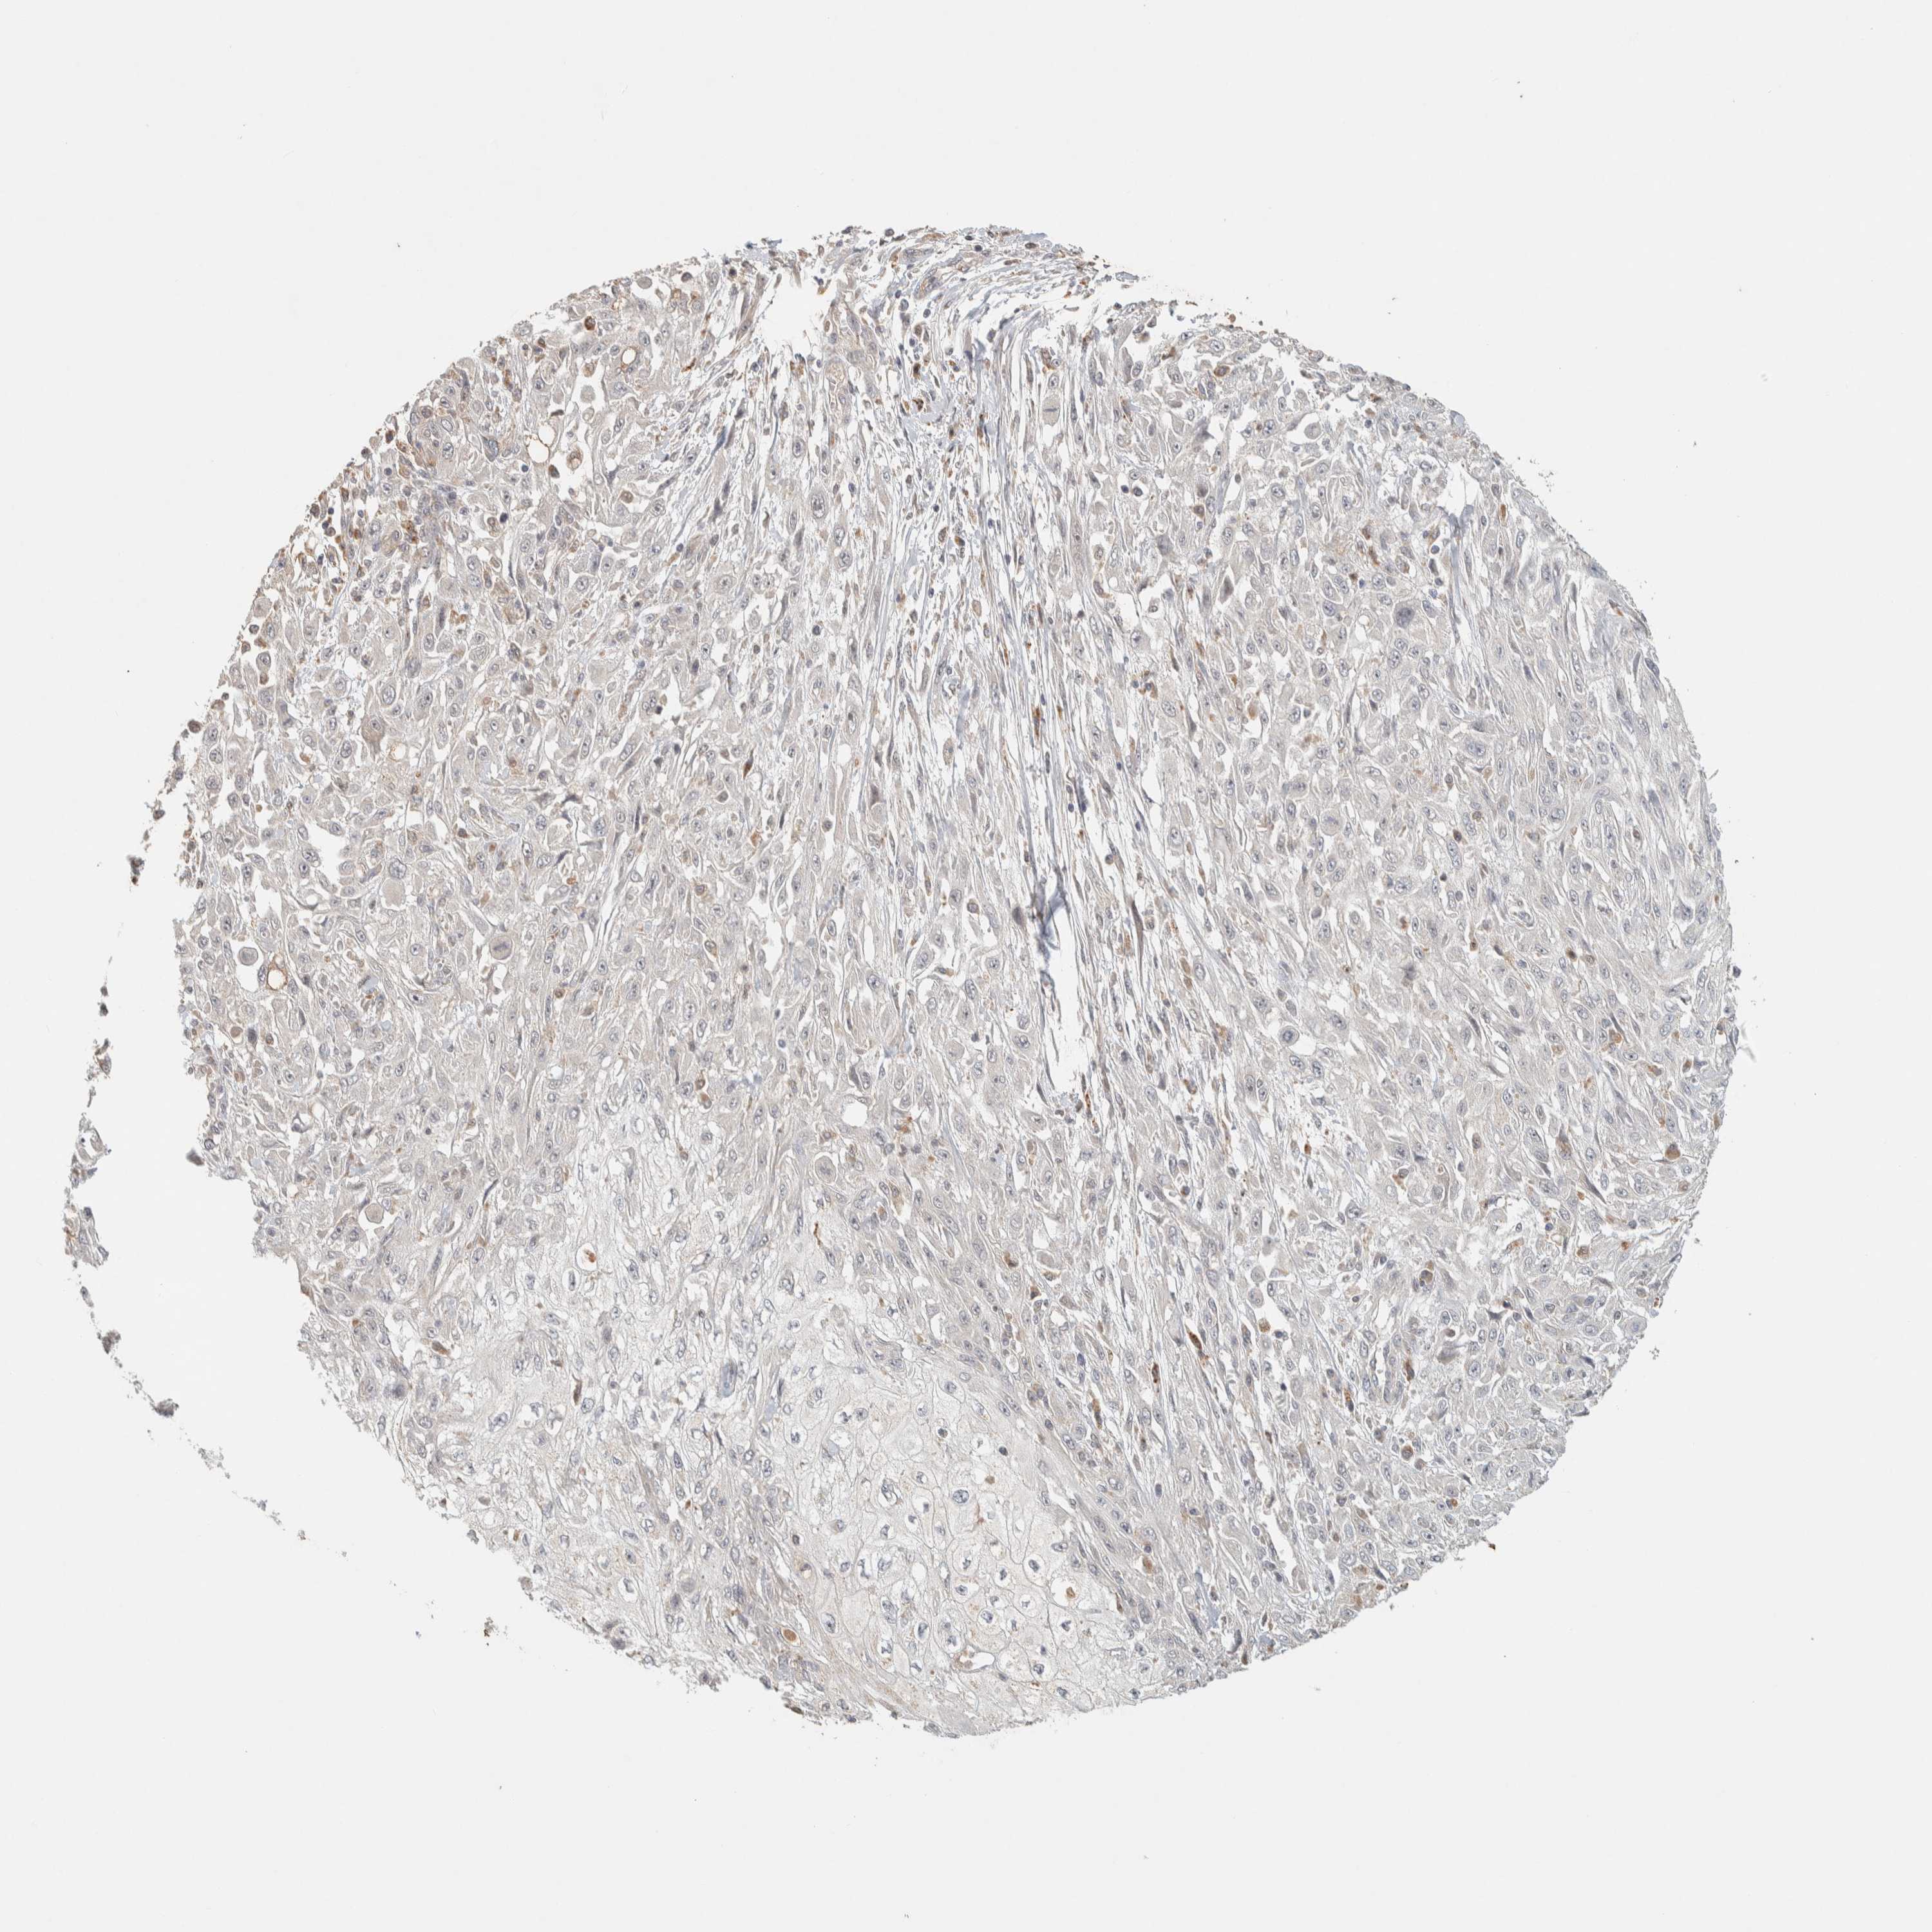

SKIN CANCER - Protein expressioni

A mouse-over function shows sample information and annotation data. Click on an image to view it in a full screen mode. Samples can be filtered based on level of antibody staining by selecting one or several of the following categories: high, medium, low and not detected. The assay and annotation is described here.

Antibody stainingi

Antibody staining in the annotated cell types in the current human tissue is reported as not detected, low, medium, or high, based on conventional immunohistochemistry profiling in selected tissues. This score is based on the combination of the staining intensity and fraction of stained cells.

Each image is clickable and will lead to virtual microscopy that enables deeper exploration of all samples and also displays staining intensity scores, fraction scores and subcellular localization as well as patient and tissue information for each sample.

Antibody HPA022824

Staining

High

Medium

Low

Not detected

Intensity

Strong

Moderate

Weak

Negative

Quantity

>75%

75%-25%

<25%

None

Location

Nuclear

Cytoplasmic/membranous

Cytoplasmic/membranous,nuclear

Squamous cell carcinoma, metastatic, NOS

Squamous cell carcinoma, NOS